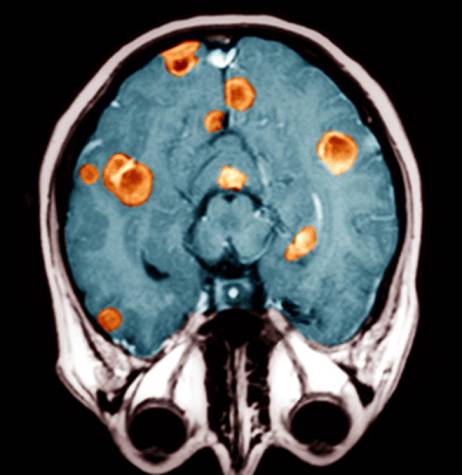

Метастазы злокачественных опухолей в головном мозге постигают каждого четвёртого больного, при посмертном исследовании их находят у шести из десяти. Метастазы выявляются на порядок чаще, чем первичные опухоли центральной нервной системы, которыми охотно занимаются нейрохирурги. Российская онкологическая статистика учитывает только первичные опухоли головного мозга и вообще первичные раки, но не знает, сколько больных имеют метастазы куда бы то ни было, а не только в головной мозг.

Любая опухоль метастазирует в мозг, но чаще всего рак лёгкого, особенно крайне агрессивный мелкоклеточный — до 80% больных, а также рак молочной железы, кишки, почки и меланома, но все они метастазируют много реже рака лёгкого. Сегодня метастазы в головном мозге находят чаще, чем в конце прошлого века, чему весьма способствуют методы нейровизуализации — КТ и МРТ и увеличение выживаемости онкологических больных в результате успехов онкологической науки. Заметно повысилась и активность онкологов, не только решающихся на лечение самых непростых больных, но и имеющих возможность выхаживать таких пациентов.

Чаще всего — в 48% случаев — метастазы в мозг связаны с раком легких. Наиболее агрессивен немелкоклеточный рак легкого — он метастазирует в мозг в 80% случаев. Реже встречаются метастазы при раке молочной железы (15%), мочеполовой системы (11%), остеогенной саркоме (10%), меланоме (9%), раке головы и шеи (6%).

При технически не удаляемых и чувствительных к противоопухолевым лекарствам видах рака, таких как молочная железа, мелкоклеточный рак лёгкого и герминогенные опухоли яичка, на первом этапе прибегают к химиотерапии, к которой в дальнейшем присоединяют облучение всего массива головного мозга. При радиочувствительных опухолях лечение можно начать с тотального облучения мозга. При опухолях не более 3,5 см и менее четырёх узлов как единственный метод эффективна стереотаксическая радиохирургия. К опухоли подводят с разных сторон несколько пучков радиоволн, они пересекаются в одном месте — там, где находится метастаз. В итоге раковые клетки уничтожаются, а окружающие здоровые ткани получают минимальную безопасную дозу. В комплексе с облучением мозга и химиотерапией результат лучше.